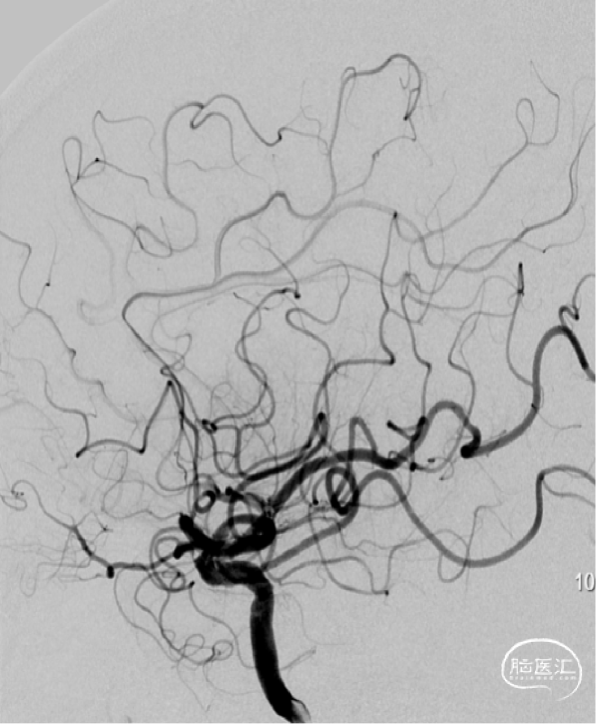

➢DSA(2023.11.10)

右侧M1段动脉瘤

左侧大脑中动脉M1段狭窄

R-DAS技术超选右侧颈内,右侧颈内动脉血管迂曲。

植入Atlas支架,动脉瘤不显示,狭窄改善。

术后正侧位。